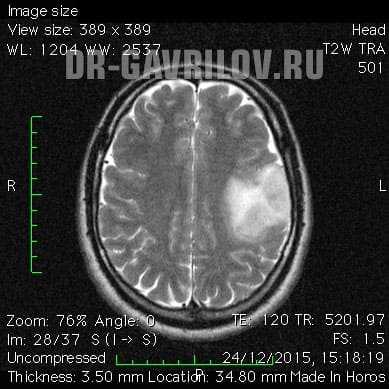

- Магнитно-резонансная томография - способна провести визуализацию опухоли в любом отделе головного мозга, выявить размер и пределы образования. В 98% случаях МРТ позволяет поставить точный диагноз. При необходимости процедура может проводиться с контрастом, что еще больше увеличивает информативность исследования.

- компьютерная (КТ) и магнитно-резонансная томография (МРТ) с контрастом - золотой стандарт при обследовании головного мозга, получаются высокоточные послойные изображения;